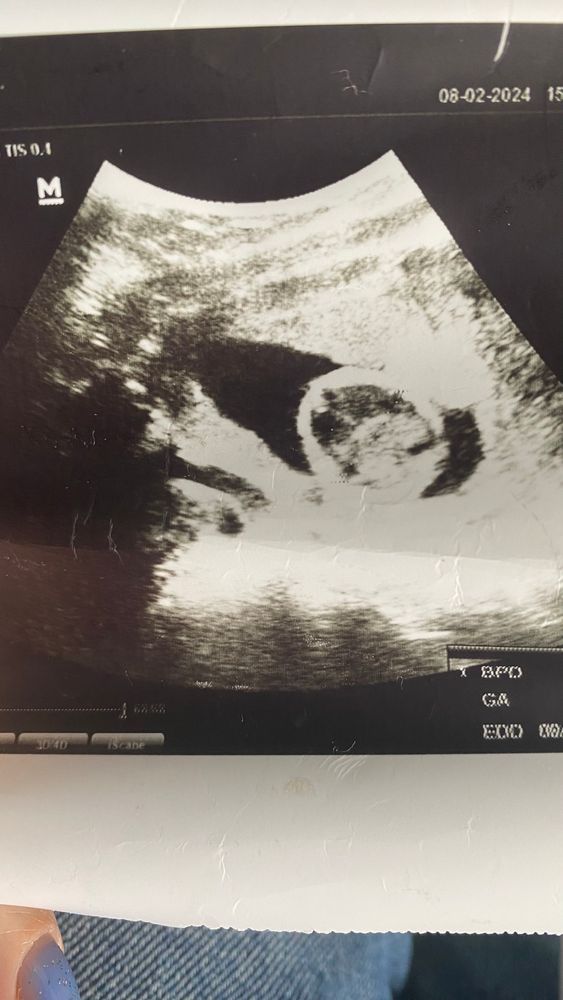

Пол по фото узи

Ну мозг у ребенка точно есть))) а пол тут не показан.

Это голова, по голове сложно определить пол)

Тут ребенок развернут совершенно другой стороной, кроме головы ничего не видать🤷

Я не вижу где тут ребенок,это голова круглая?

Первый скрининг🌹 Кого вы видите?) УЗИ на 13 неделе